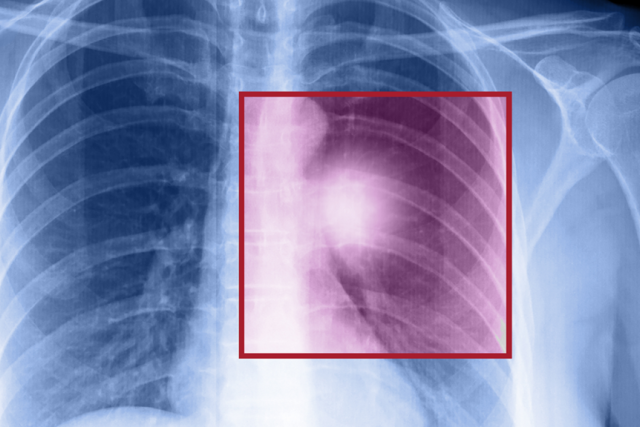

X-ray scan of a lung cancer tumor.

Scan of a lung cancer tumor.

Lung cancer is the top-killing cancer among Americans, but certain high-risk people who have smoked, or currently smoke, can undergo a low-dose CT lung scan that reduces death rates by at least 20%.

“Lung cancer deaths exceed deaths from breast, prostate and colon cancer combined,” says Denise Aberle, MD, a diagnostic radiologist at UCLA Health. “We now have a screening test that can detect lung cancer in asymptomatic individuals, potentially at its earliest stage when local therapy can be curative.”